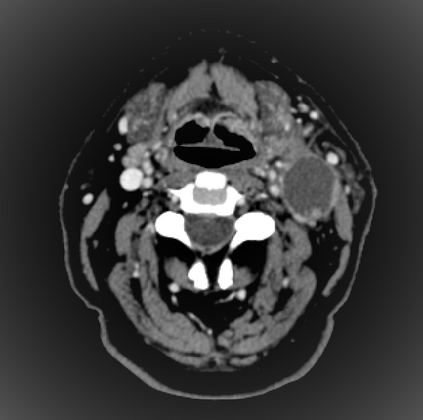

Organ at risk (OAR) segmentation is a critical process in radiotherapy treatment planning such as head and neck tumors. Nevertheless, in clinical practice, radiation oncologists predominantly perform OAR segmentations manually on CT scans. This manual process is highly time-consuming and expensive, limiting the number of patients who can receive timely radiotherapy. Additionally, CT scans offer lower soft-tissue contrast compared to MRI. Despite MRI providing superior soft-tissue visualization, its time-consuming nature makes it infeasible for real-time treatment planning. To address these challenges, we propose a method called SegReg, which utilizes Elastic Symmetric Normalization for registering MRI to perform OAR segmentation. SegReg outperforms the CT-only baseline by 16.78% in mDSC and 18.77% in mIoU, showing that it effectively combines the geometric accuracy of CT with the superior soft-tissue contrast of MRI, making accurate automated OAR segmentation for clinical practice become possible. See project website https://steve-zeyu-zhang.github.io/SegReg